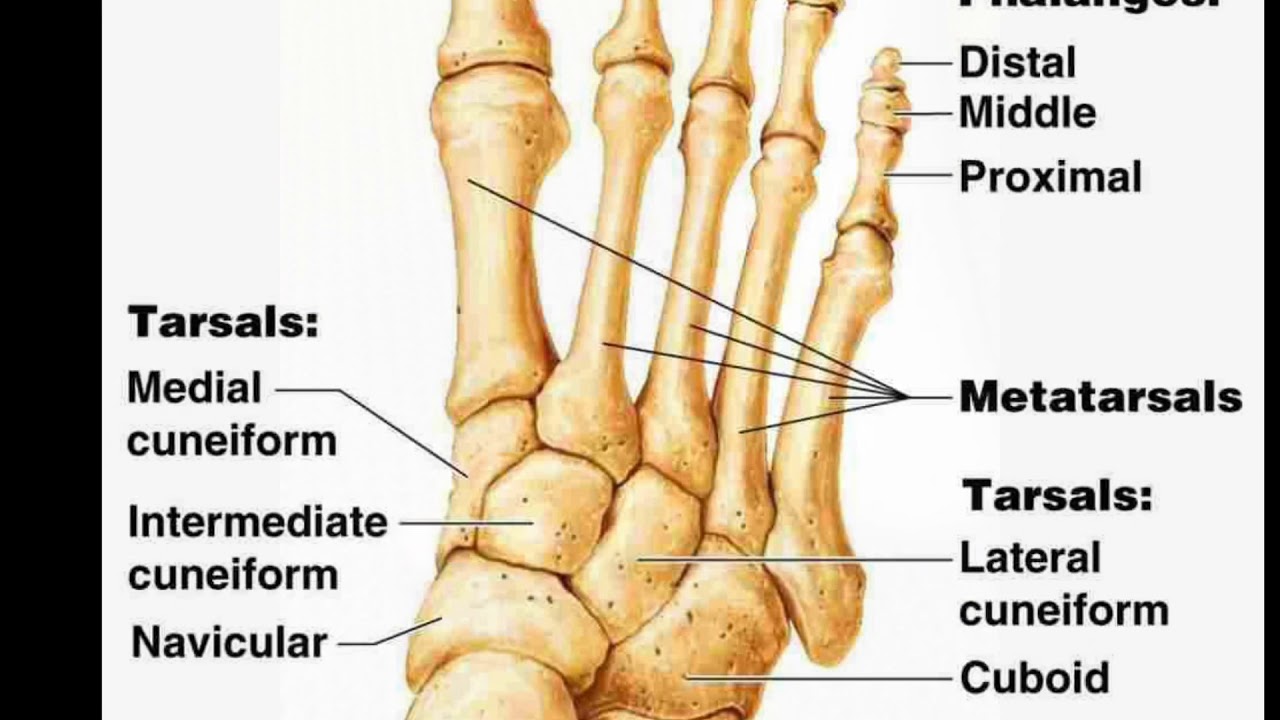

Os naviculare перевод

Os naviculare перевод 144 фотографий